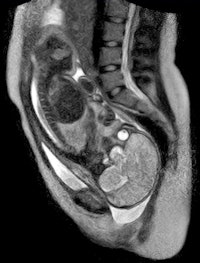

German physicians and healthcare providers at Charité University Hospital in Berlin recently followed the birth of a child on an open MRI system.

The hospital reported that the birth on November 20 was without complications and both mother and baby are doing well. The baby, a boy, weighed 2,585 grams (5.7 lb) and was 47 cm (18.5 inches) in length.

The study was performed as part of a two-year research and development project on open MRI involving a novel fetal monitoring system that allowed the monitoring of the child's heartbeat during the birth process. The researcher team, led by radiologist Ulf Teichgräber, MD, noted that the open design of the scanner provided easy access to mother and child during the study.

The research team plans to explore the birth process and movements of the unborn child and the mother's pelvis to better understand why approximately 15% of pregnant women need a cesarean section due to the baby not moving properly into the birth canal.